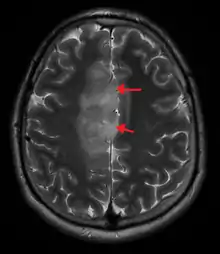

An X-ray computed tomography (CT) or magnetic resonance imaging (MRI) scan is necessary to characterize the anatomy of this tumor as to size, location, and its heter/homogeneity. However, final diagnosis of this tumor, like most tumors, relies on histopathologic examination (biopsy examination).[3]

If resected, the surgeon will remove as much of this tumor as possible, without disturbing eloquent regions of the brain (speech/motor cortex) and other critical brain structure. Thereafter, treatment may include chemotherapy and radiation therapy of doses and types ranging based upon the patient's needs. Subsequent MRI examination are often necessary to monitor the resection cavity.